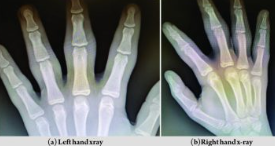

손가락 피부 비후증(pachydermodactyly)은 손가락 관절 부위 피부가 비정상적으로 두꺼워지는 매우 드문 양성 섬유종증입니다. 주로 젊은 남성에게서 2~4번째 손가락의 근위지간관절(손가락 마디) 부위에 양측성으로 발생하며, 통증이나 운동 장애가 거의 없고, 외형상 부종(붓기)만 나타나는 것이 특징입니다.

♼ 진단: 단순 방사선 촬영에서는 뼈의 이상 없이 연부조직만 두꺼워진 것이 보이고, MRI에서도 관절 내부 이상 없이 연부조직 비후만 관찰됩니다.